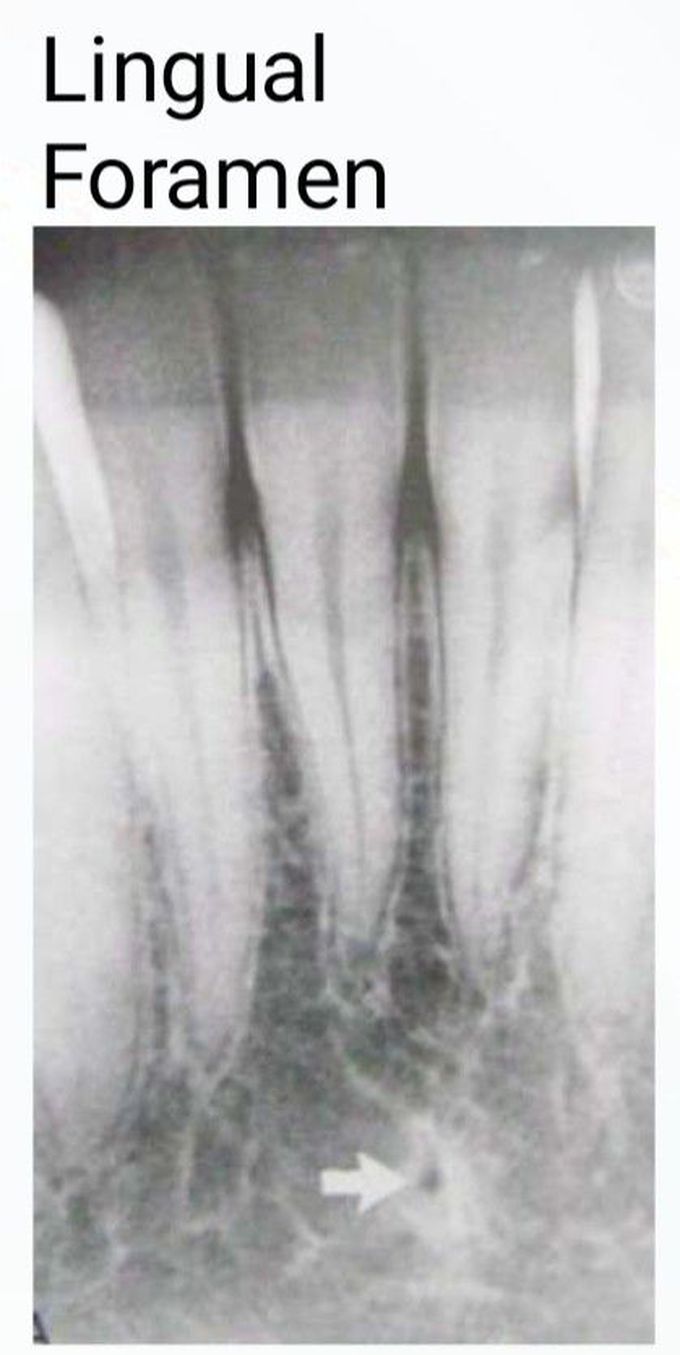

Lingual Foramen

Lingual foramen (LF) and its intra-osseous canal are important landmarks located in the anterior region of the mandible.